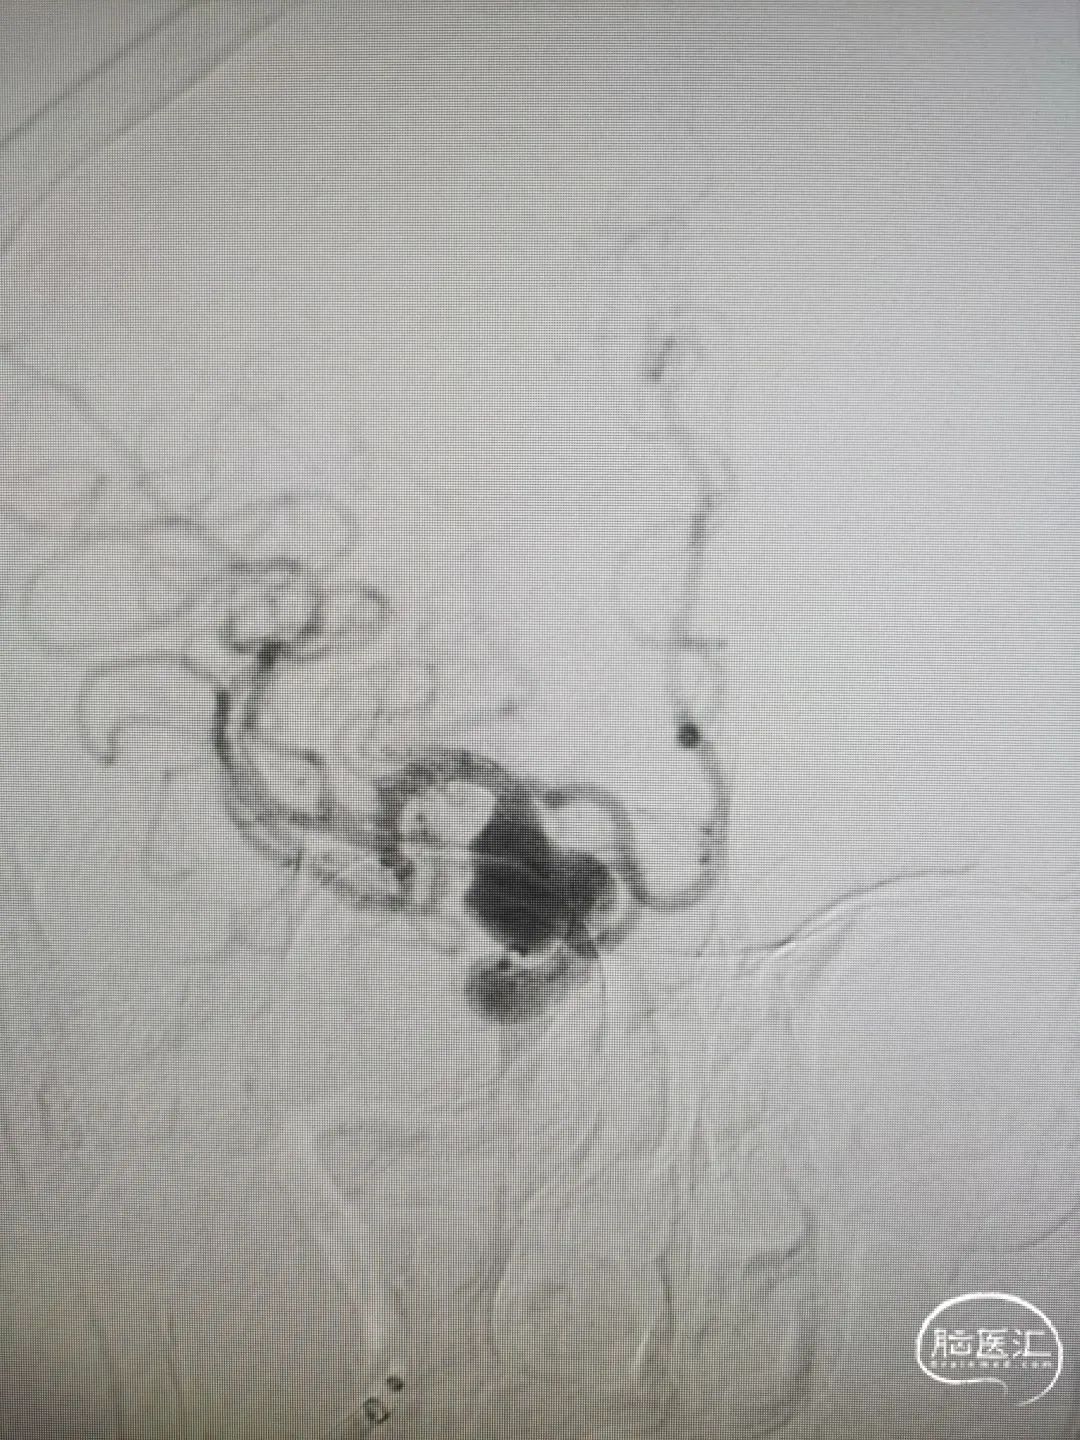

图4右颈内动脉海绵窦段起始部类圆形瘤样扩张,最大约19mm╳14mm,瘤颈约14mm,瘤内射流明显,载瘤动脉远端5mm,近端4.5mm。

8F常规指引到右颈内动脉开口做近端支撑。Synchro 0.014 200微导丝及XT-27微导管引导CAT 5导管同轴越过右颈内动脉瘤至右大脑中动脉M1。由于动脉瘤颈较大,微导丝引导XT-27微导管,无法直接通过,采用瘤内成袢技术通过。选取Surpass Streamline 5mm╳30mm经CAT 5导管释放,并行微导丝及CAT 5导管按摩。

图5